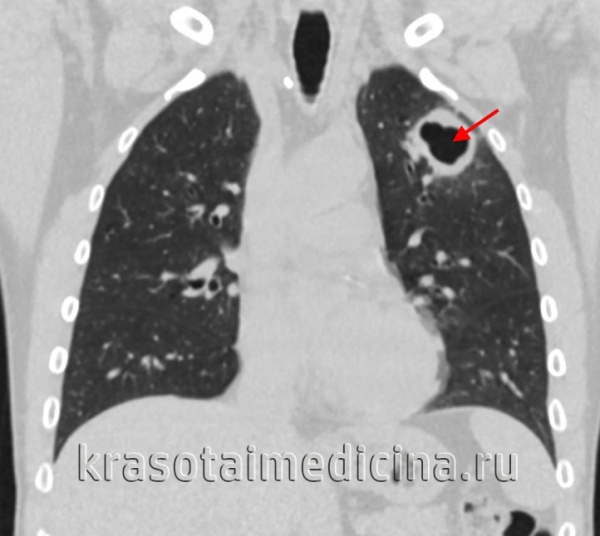

(Справа) На аксиальном КТ срезе определяется большое кистозное объемное образование в воротах печени и в области головки поджелудочной железы — конгломерат увеличенных лимфоузлов с изменениями по типу казеозного некроза в результате микобактериальной инфекции (М. tuberculosis). (Слева) На аксиальном КТ срезе визуализируется полость и распространенные (в нескольких долях) изменения по типу бронхоальвеолярной инфекции легких, типичные для активной формы туберкулеза. Эта пациентка — молодая женщина, студентка из Азии, приехавшая на учебу «по обмену».